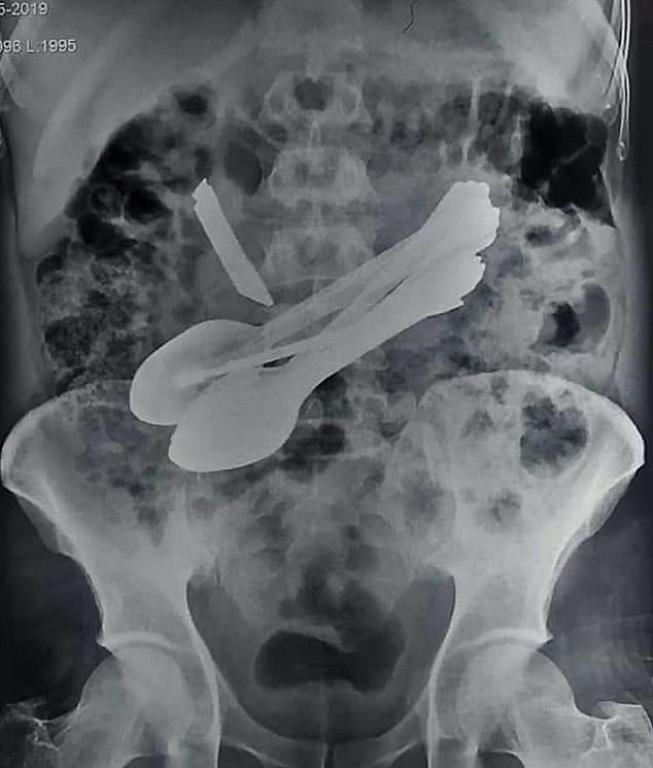

Doctors were stunned to discover a knife, eight spoons and a screwdriver inside a 35-year-old man, who had been complaining of unbearable stomach pain.

X-ray test revealed spoons in his stomach, but it was just the tip of the iceberg. Doctors also saw a knife that seemed to be piercing through the patient’s stomach.

One of the doctors said: “We could already see the tip of the knife protruding from inside his stomach. Later we operated him without wasting any time but discovered more objects inside.

“There was a knife, eight spoons, two screwdrivers and two toothbrushes inside as we continued to operate his stomach.”

A metal bar was also retrieved from his stomach. It is understood the 35-year-old was suffering from a psychiatric disorder that caused him to eat objects.